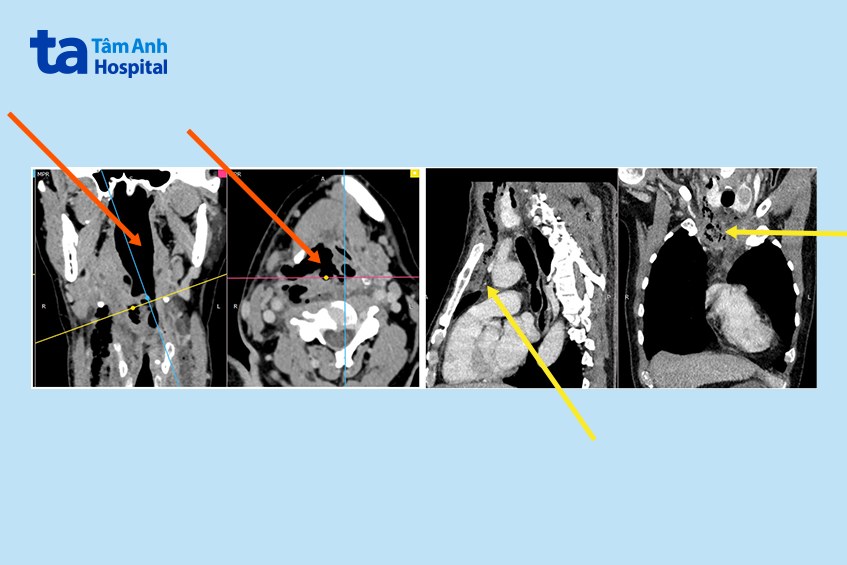

Trên phim chụp cắt lớp vùng cổ ngực (CT scan) cấp cứu cho thấy hình ảnh ổ dịch (ổ áp xe) cùng nhiều hốc khí lan rộng từ sàn miệng qua vùng cổ bên phải đến chỗ vỡ xoang lê (ở thành trước bên họng). Ổ áp xe lan rộng toàn bộ vùng cổ, phía trước lan qua khí quản đến cổ bên phải, phía sau lan ra đến cột sống cổ và sau khí quản, phía dưới đi sâu vào trong trung thất trước (phần ngực ở giữa hai phổi, phía trước tim và ngay sau xương ức).